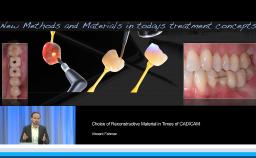

This lecture presents a concept for choosing the type of reconstruction and material for highly esthetic outcomes. Due to the number of restorative possibilities, the selection of an ‘ideal’ material is getting more and more complex. Advantages of all-ceramic materials over traditional metal-ceramics include their tooth-like color and their enamel-like translucency. The main limitation of ceramics is their brittleness, leading to a risk for fracture during clinical service. This lecture discusses the development of modern ceramics with increased stability to reduce this risk, with a focus on high-strength ceramic zirconia and its potential as an alternative to metal. For the processing of zirconia, numerous computer-aided manufacturing procedures are available today. Moreover, multiple clinical studies show promising results for zirconia-based tooth and implant reconstructions.

- discuss the clinical applications of high-strength zirconia

- describe the CAD/CAM processing of zirconia reconstructions